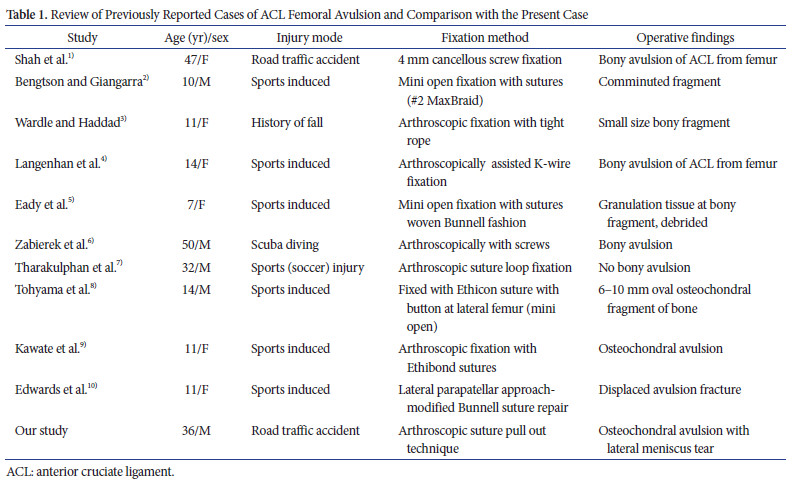

Dans la plupart des cas précédemment connus, les chirurgiens ont utilisé une technique ouverte ou mini ouverte qui peut potentiellement conduire à une arthro-fibrose. Seules deux études antérieures ont utilisé des techniques de fixation arthroscopique : l'une utilisant des fils K et l'autre utilisant un TightRope (Arthrex). L'utilisation d'un fil K intra-articulaire nécessite une procédure supplémentaire pour le retirer. Le TightRope est un dispositif de traitement chirurgical relativement coûteux mais efficace. Cette technique est unique car elle a été réalisée sur un cas de lésion multi-ligamentaire du genou avec une déchirure du ménisque réparable. Ces trois éléments anatomiques ont été réparés et guéris chez cet adulte. Le tableau 1 résume les rapports de cas précédents et comporte le profil du patient, le type de blessure et les techniques utilisées.

Dans la plupart des cas précédemment connus, les chirurgiens ont utilisé une technique ouverte ou mini ouverte qui peut potentiellement conduire à une arthro-fibrose. Seules deux études antérieures ont utilisé des techniques de fixation arthroscopique : l'une utilisant des fils K et l'autre utilisant un TightRope (Arthrex). L'utilisation d'un fil K intra-articulaire nécessite une procédure supplémentaire pour le retirer. Le TightRope est un dispositif de traitement chirurgical relativement coûteux mais efficace. Cette technique est unique car elle a été réalisée sur un cas de lésion multi-ligamentaire du genou avec une déchirure du ménisque réparable. Ces trois éléments anatomiques ont été réparés et guéris chez cet adulte. Le tableau 1 résume les rapports de cas précédents et comporte le profil du patient, le type de blessure et les techniques utilisées.